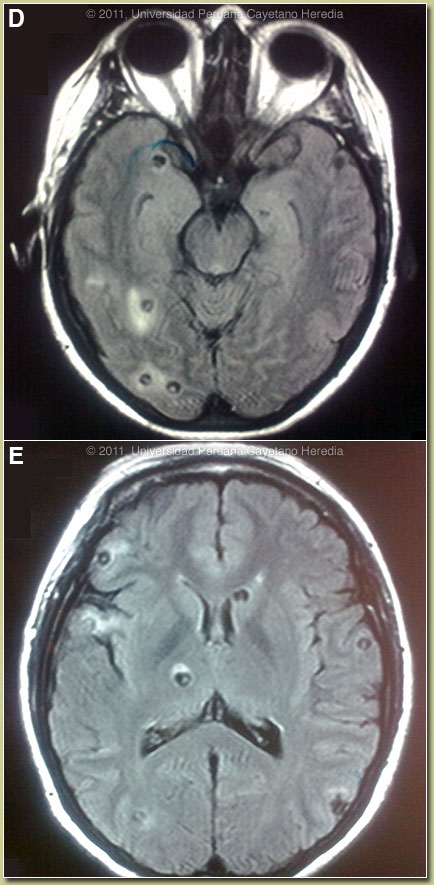

Discussion: The biopsy showed a large cystic structure with a homogenous histiocytic wall and eosinophils surrounding the cystic space. Western blot was positive for cysticercosis. MRI of the brain showed at least 30 cysts with perilesional edema and a hyperintense intracystic point on FLAIR images corresponding to the scolex of the larvae [Images D and E]. No intraventricular lesions or signs of intracranial hypertension were seen. No calcified lesions were seen on CT scan (not shown).